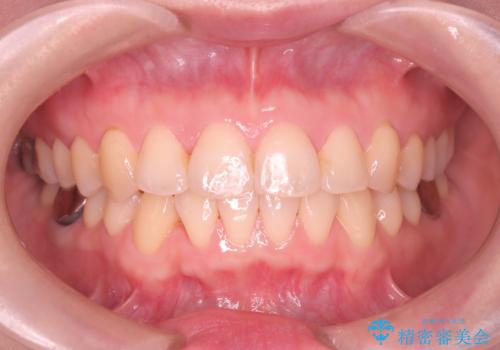

- 前歯の翼状捻転の改善を希望してこられた患者様です。

下顎の叢生はインビザラインで解決することがきましたが、上顎の捻転が完全には改善できなかったため、上顎は途中からワイヤーを用いて治療を行っています。

捻転の改善はインビザラインで苦手とするところですので、うまく治らない場合はワイヤーを提案しています。